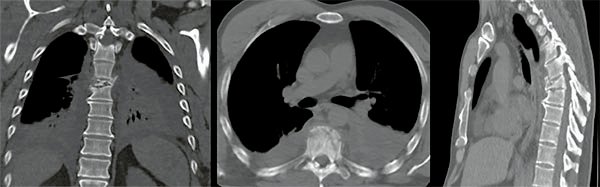

Figura 1:

Caso 24. Hombre 21 años con politraumatismo por accidente vial. A y B: Fractura del cóndilo occipital izquierdo. C: Fractura expuesta del húmero izquierdo y clavícula. D: Contusión pulmonar más hemotórax derecho.